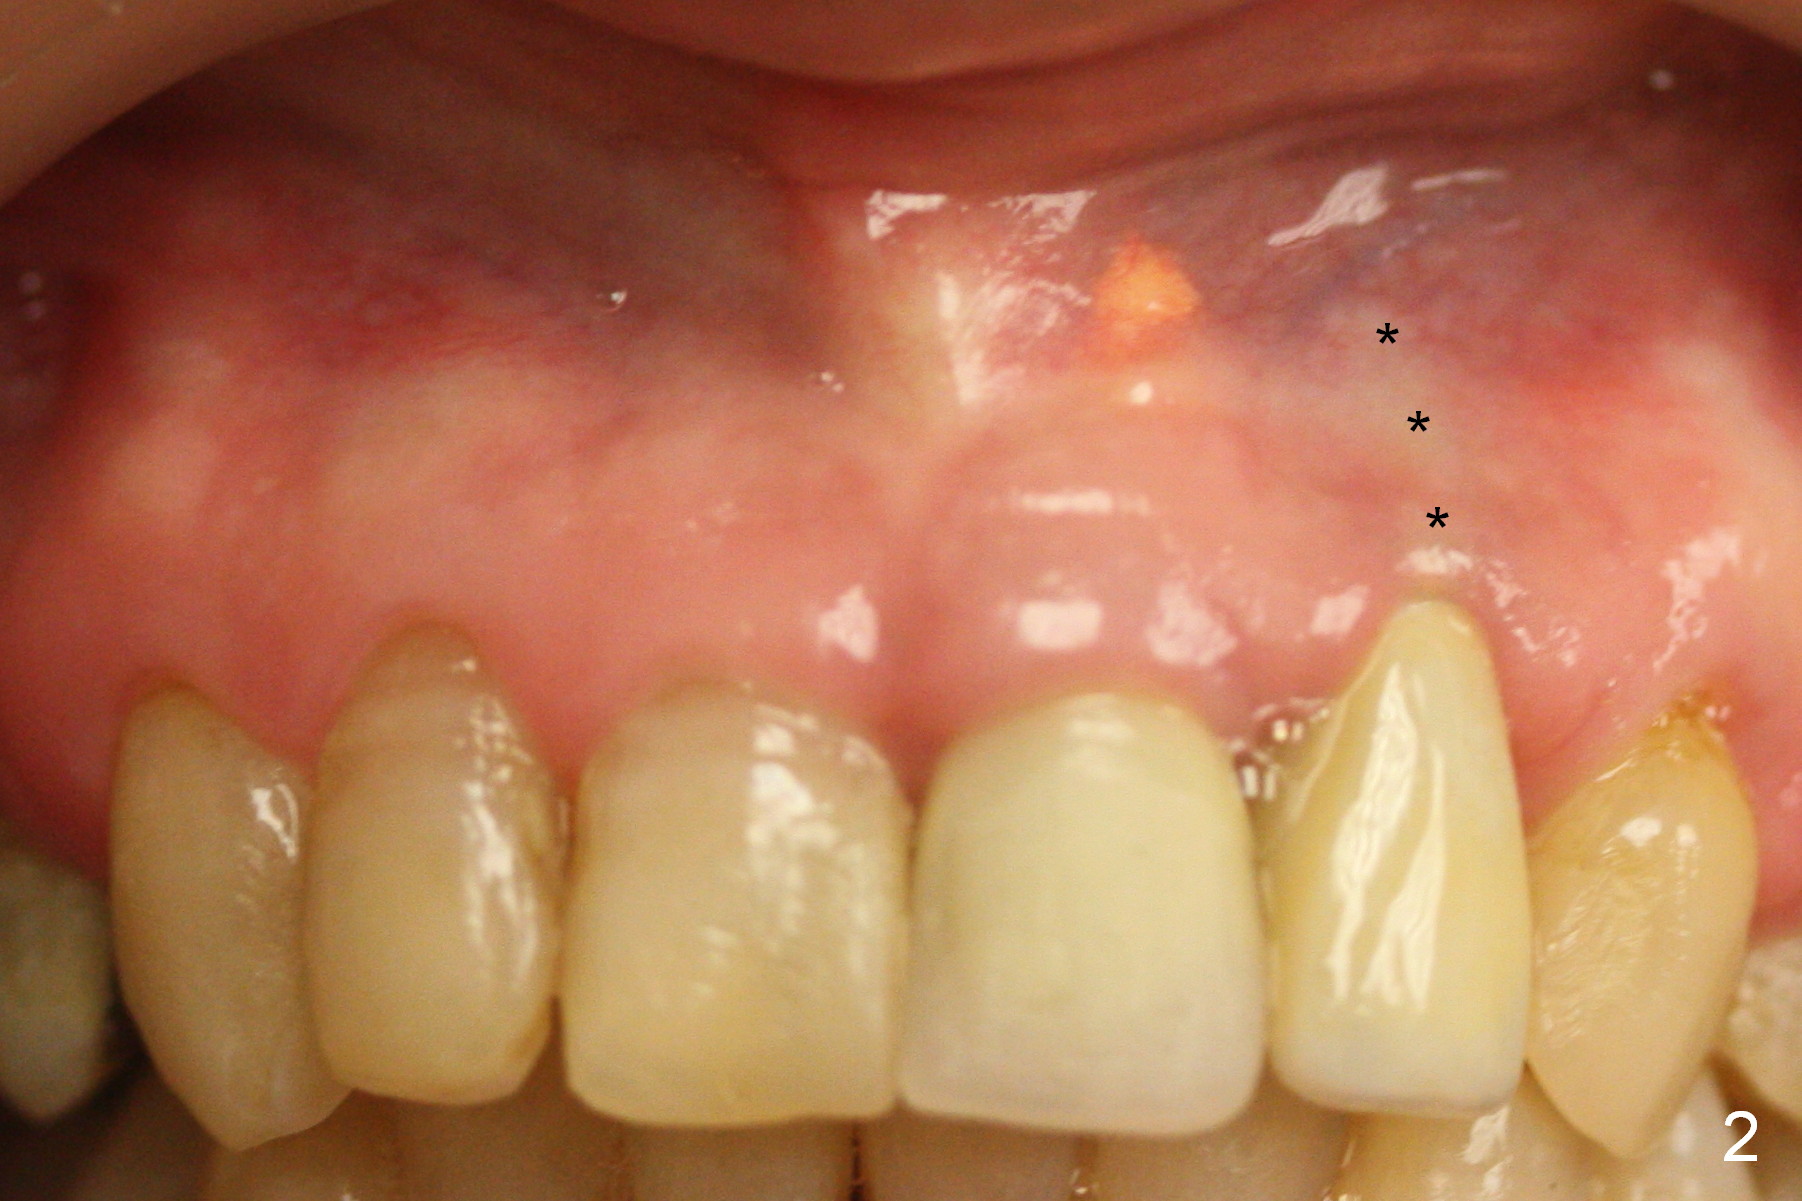

The 57-year-old lady does not like the crown at the site of #10 immediately when it is cemented (Fig.1). When the upper lip is retracted, it appears that the implant is immediately underneath the gingiva (Fig.2 *). It is slightly tender when palpated. The patient refuses CBCT. When the buccal flap is raised, the implant is found to be exposed buccally (Fig.3). When it is removed, the coronal portion of the palatal wall is thin (Fig.4). It appears that there is bone in the mid and apical thirds of the palatal wall, where an osteotomy is initiated using a 1.2 mm pilot drill. When the latter reaches 18 mm from the crest, the nasal floor appears to be perforated. The latter is confirmed by PA (Fig.5). As the osteotomy are increasing in diameter, force is applied as palatally as possible without perforating the palatal wall too much. When a 3.5x20 mm implant is placed (30 Ncm), it is palatal to the labial wall. The defect is filled by allograft and Osteogen, covered by long termed resorption membrane. The buccal flap is sutured (Fig.7). A proposal to place gingival graft is rejected. The implant is shown to have been positioned more or less normally (Fig.8). A removable temporary appliance is fabricated. Periodontal dressing is applied.